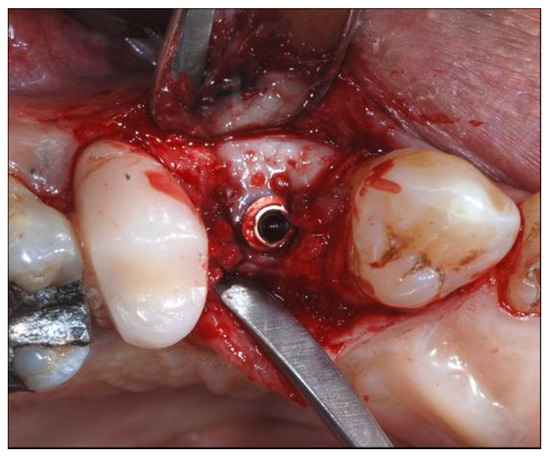

2.4. Surgical Phases